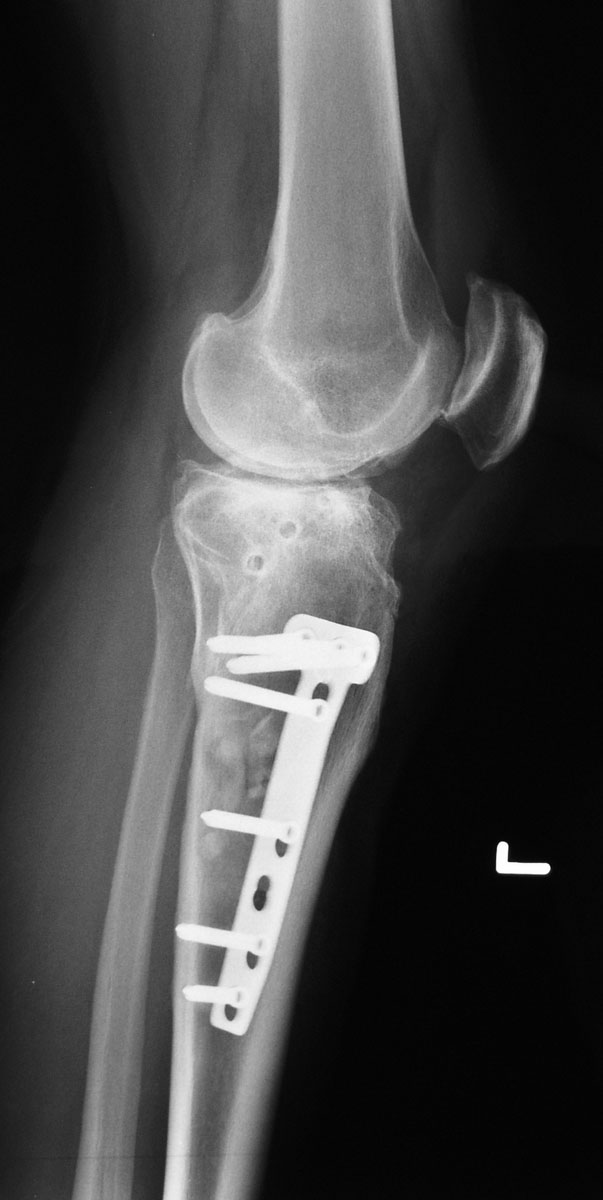

Röntgenbilder Salemspital Bern, 12. August 2005